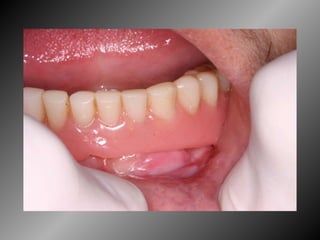

Granuloma Piogênico Lesão Nodular Séssil ou pediculada Avermelhada ou vinhosa Sangramento espontâneo e áreas de micro-ulceração superficial

Granuloma Piogênico Lesões nodulares de coloração avermelhada ou vinhosa Provavelmente uma reação inflamatória exagerada ao trauma menor Crescimento rápido, às vezes sangramento espontâneo Ocorre em qualquer idade mas parece mais freqüente em adultos jovens e adolescentes  Localização mais comum: gengiva (NEVILLE,2001)

Granuloma Piogênico Lesões mais antigas, são menos vasculares e mais fibrosas Papila interdental e regiões anteriores são áreas preferenciais, principalmente por vestibular (BORK,1996)

Granuloma Piogênico LesãoNodular Séssil ou pediculada Avermelhada ou vinhosa Sangramento espontâneo e áreas de micro-ulceração superficial

Granuloma Piogênico Lesõesnodulares de coloração avermelhada ou vinhosa Provavelmente uma reação inflamatória exagerada ao trauma menor Crescimento rápido, às vezes sangramento espontâneo Ocorre em qualquer idade mas parece mais freqüente em adultos jovens e adolescentes Localização mais comum: gengiva (NEVILLE,2001)

Granuloma Piogênico Lesõesmais antigas, são menos vasculares e mais fibrosas Papila interdental e regiões anteriores são áreas preferenciais, principalmente por vestibular (BORK,1996)